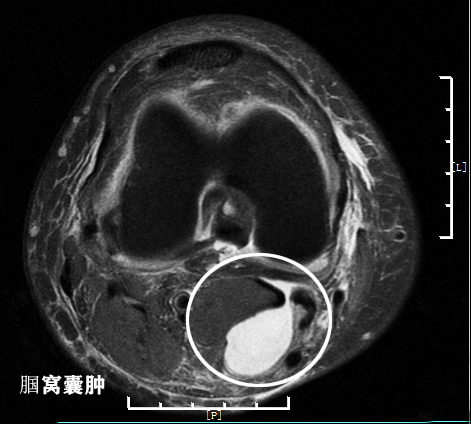

第四,腘窝囊肿。腘窝囊肿多见于关节内软骨损伤、关节退变以后导致了关节内的滑膜炎症,出现积液。积液在关节内找到了一个软弱的位置向关节后方突入,最终形成囊肿。谢医生写过关于囊肿的科普文章,有兴趣的朋友可以看一下。一般腘窝囊肿的核磁影像是这样的。